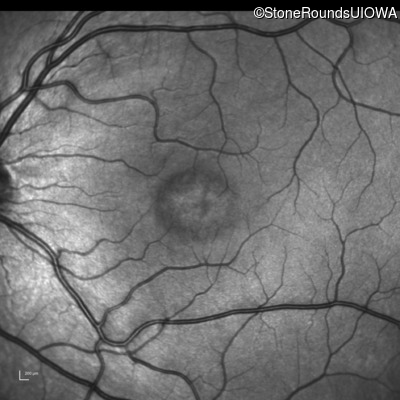

This 6 year old boy first experienced difficulty reading and seeing the blackboard at age 5.

| Age at visit: 6 years |